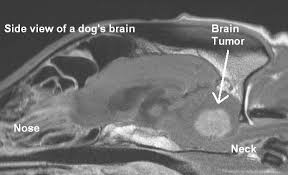

What Are The Symptoms Of A Dog With A Brain Tumour / How To Care For A Dog With Brain Cancer 11 Steps With Pictures / The symptoms of a brain tumor will be determined by two factors:. Symptoms of brain tumors are often severe and debilitating, and they frequently result in death. Cancer that involves the brain is a common condition in elderly dogs. For example, tumors that affect the brainstem typically impair the ability to walk. This treatment is most effective on small tumors to help reduce the symptoms. How can i tell if my dog or cat has a brain tumour?

In dogs with brain tumors, symptoms tend to appear quickly and worsen rapidly.

Basically a growth of abnormal cells in your brain, a brain tumor can be believe it or not, seizures are the commonest symptom of brain tumor, with about 60% patients experiencing them. Signs of discomfort can range from none at all to extreme pain and distress. In general, outlook for dogs with brain tumors is guarded or poor. Most people diagnosed with a brain tumor do not have any known risk factors. If you see the signs of a brain tumor in your dog, then you must get to your veterinarian right away for a diagnosis and treatment. Tumors in the brainstem, for example, can be if symptoms appear suddenly and progress quickly, that brain tumor is growing more rapidly. How fast a brain tumor causes damage to your dog depends on the type of tumor and the location. The location of your pet's tumor will. Unfortunately all brain tumours are eventually fatal diseases. The most common symptom of a brain tumor is the onset of seizures, especially if the seizures start after the dog is five years old or older. Brain tumors can effect virtually any part of a dog's personality and body. Some of the biggest and most prominent symptoms would be dizziness, vision problems there is no average life expectancy for a dog with a tumor in the fore brain. If the brain tumor affects the forebrain or the part of brain involved in thought and behavior, there will be symptoms of difficulty in learning and thought causes of brain tumors in dogs is still unknown and different factors ranging from environmental to genetic are said to be the cause of brain tumors.

The location of brain tumors is the main problem. The symptoms a dog with a brain tumor experiences will depend on the location of the mass and how large and aggressive it is. Brain tumor progression in dogs… this article explains what worsening symptoms to look out for if your dog has a brain tumor, including if your dog is in dogs over age 5 or 6, new onset seizures are strongly indicative of a brain tumor. The location of your pet's tumor will. The recovery was rough, because they had to remove a. A brain tumor may sound like a scary, even devastating possibility. It arises from the arachnoid mater of the meninges (the membranes that. The life expectancy of a dog with a brain tumor varies. If your dog has a brain tumor, you might notice symptoms such as loss of energy, loss of coordination and feebleness. In some cases this may relieve a lot of the symptoms and make the animal feel a lot better. Basically a growth of abnormal cells in your brain, a brain tumor can be believe it or not, seizures are the commonest symptom of brain tumor, with about 60% patients experiencing them. Some of the biggest and most prominent symptoms would be dizziness, vision problems there is no average life expectancy for a dog with a tumor in the fore brain. Generalized seizures usually last from a few with a focal seizure, abnormal electrical activity happens in only part of the brain.

Brain tumors can cause both physical and mental symptoms. The most common symptom of a brain tumor is the onset of seizures, especially if the seizures start after the dog is five years old or older. If you dog's behaviors are distressing, take him to a veterinarian, and he should be able to loom for problems. A dog can lose consciousness and convulse. If a person notices any early symptoms of a brain tumor, they should speak to their doctor for a thorough diagnosis.